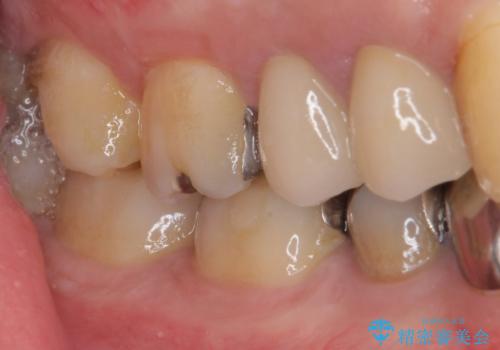

ゴールドインレーは銀歯のインレーやセラミックインレーと比べ、「技工操作の精度が高く、適合が著しく良い」というメリットがあります。特に上の奥歯は歯科医師の操作が行いにくいため、「適合の良さ」は再治療のリスクを防ぐ上でとても重要な要素となります。

上の奥歯は金属色が見えることもないため、審美的な問題は全くありません。

咬み心地はとても良好で、全く違和感がなく、患者様には大変満足していただきました。